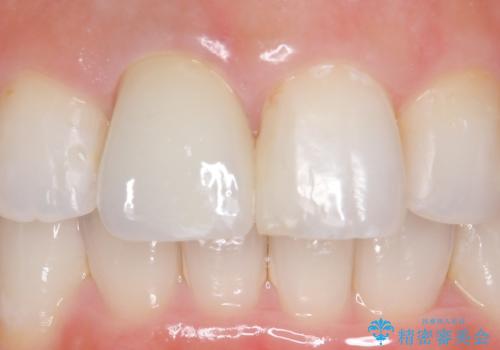

- 右上1の前歯の見た目が気になるので被せ物をやり替えたいといらっしゃった方の症例です。

再根管治療終了後、オールセラミッククラウン(スペシャル)によって隣在歯に合わせた補綴を行いました。

前歯の補綴ではオールセラミッククラウンを希望される患者様が多いですが、オールセラミッククラウンの中でも、エコノミー、スタンダード、スペシャル、エクセレントとランクがあります。

その中でも特に審美性が高いのがスペシャル、エクセレントです。スペシャル、エクセレントは口腔内写真をもとに熟練の技工士が、患者様の口腔内に合わせたオーダーメイドのクラウンを製作致します。